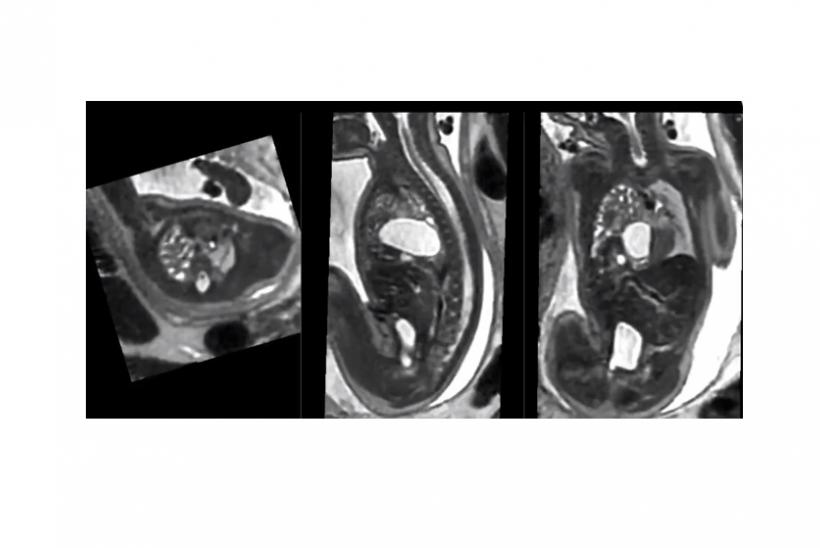

image of MRI scan

Images courtesy of Alena Uus and Maria Deprez

MRI scanning can more precisely define and detect head, neck, thoracic, abdominal and spinal malformations in unborn babies, finds a large multidisciplinary study led by Evelina London Children’s Hospital, Great Ormond Street Hospital (GOSH) and University College London (UCL).

Recent research has concentrated on correcting for fetal movement in fetal brain MRI and, more recently, for imaging the developing heart. However, there is an increasing demand to assess the entire fetus with MRI and research from the School of Biomedical Engineering & Imaging Sciences at Evelina London Children’s Hospital (BMEIS), have recently been able to develop a method to refine and correct the images captured, of the whole fetal body, even if there is movement during the scan.

New approaches to imaging the fetal body with MRI allows both motion correction of the fetal images and volume reconstructions of body organs and defects. Researchers say this improves visualisation and therefore detection and characterisation of abnormalities.